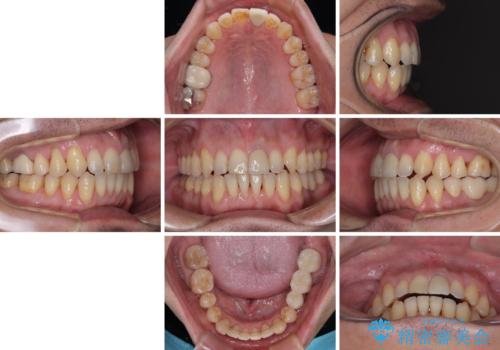

外科処置は希望されなかったので、開咬の改善は限界があると事前にお話ししていたため、上下前歯が完全に接触する前に、もう十分改善したとのことで治療を終了しました。

インビザラインを毎日22時間しっかりと装着してくださったので、我々も驚愕するほどの治療成果が達成されました。